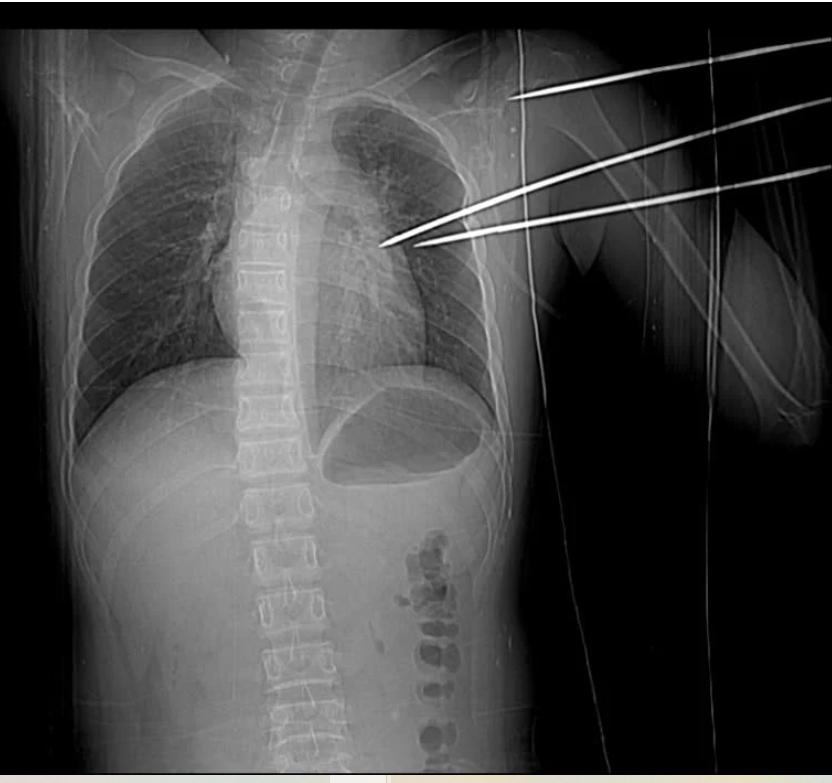

Bệnh nhân nhập viện với dị vật kim loại sắc nhọn, dạng đinh ba tự chế, đâm thẳng từ phía sau vai trái, xuyên sâu vào lồng ngực.

Khi nhập viện, bệnh nhân trong tình trạng tỉnh táo, mạch và huyết áp tạm thời ổn định. Tuy nhiên, kết quả thăm khám nhanh chóng cho thấy tình hình nguy cấp: một dị vật kim loại sắc nhọn, dạng đinh ba tự chế, đâm thẳng từ phía sau vai trái, xuyên sâu vào lồng ngực.

Đặc biệt, dị vật này vẫn còn cắm trong cơ thể, đập theo từng nhịp tim của bệnh nhân, tiềm ẩn nguy cơ đe dọa tính mạng bất kỳ lúc nào.

Dị vật kim loại sắc nhọn, dạng đinh ba tự chế, đâm từ phía sau vai trái, xuyên sâu vào lồng ngực, gây tổn thương phổi và tim của bệnh nhân.

Hình ảnh chụp X-quang và CT cho thấy dị vật không chỉ xuyên qua mặt sau vai trái mà còn xuyên qua mô thùy trên phổi trái, đâm vào thành bên thất trái của tim, gây tràn máu màng tim – một tổn thương cực kỳ nghiêm trọng.